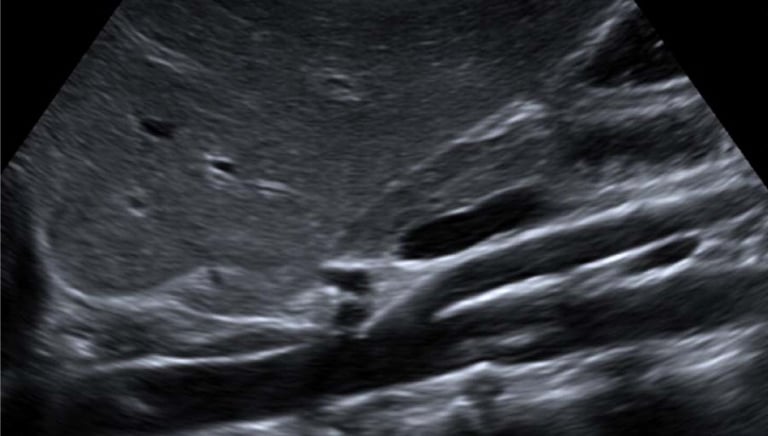

An abdominal aortic ultrasound is a non-invasive imaging test that uses sound waves to evaluate the aorta — the main blood vessel that carries blood from your heart to the rest of your body. The exam focuses on the portion of the aorta that passes through the abdomen.

This test is commonly performed to detect an abdominal aortic aneurysm (AAA) — a dangerous enlargement or bulging of the aorta that can lead to life-threatening complications if not found early.

The sonographer will move a small probe (transducer) over your skin to capture images of the aorta.